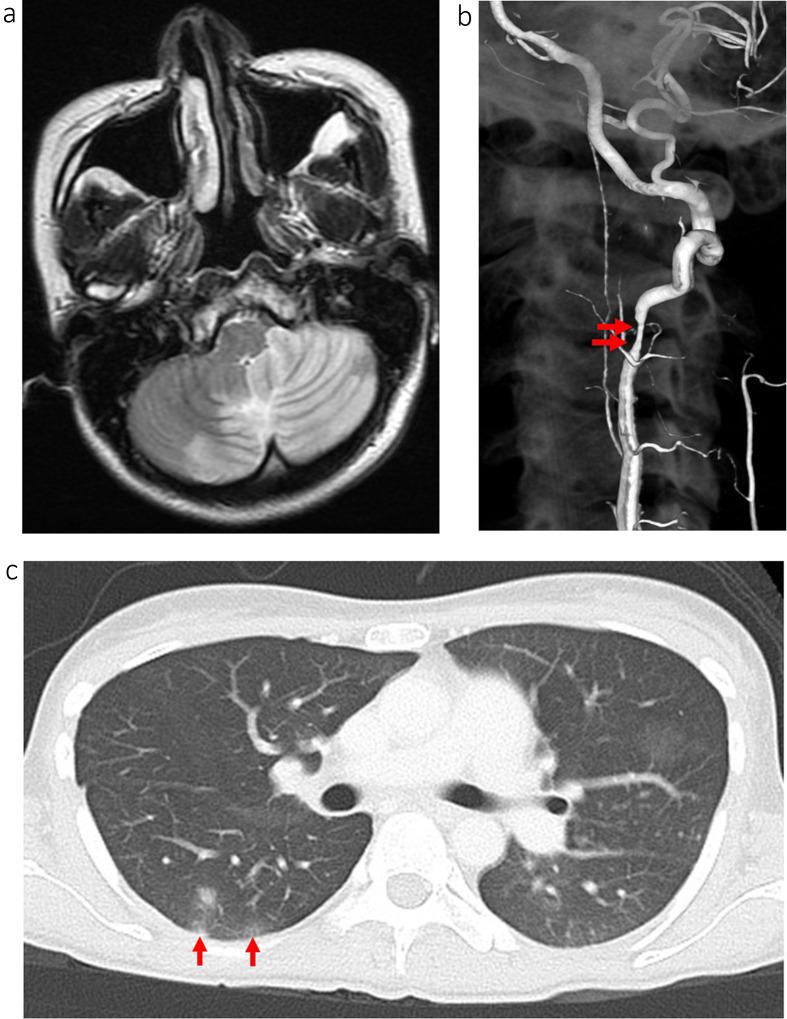

The patient was a 28-year-old female with no medical history. She was transferred our hospital due to sudden onset of vertigo and vomit. A computed tomography on day 2 revealed the hydrocephalus due to the cerebellar infarction, and she underwent posterior fossa decompression for cerebellar infarction. An angiography on day 8 revealed a left vertebral artery dissection, which was suspected be the etiology. Afterwards, a sudden fever of 39 degrees developed on day 38. She was diagnosed with aspiration pneumonia and treated with ampicillin/sulbactam but was still febrile at the time of transfer for rehabilitation. Treatment continued with levofloxacin, the patient had no fever decline, and she was readmitted to our hospital. Readmission blood cultures (3/3 sets) revealed C. striatum, and an echocardiogram revealed an 11 mm long mitral valve vegetation, leading to NVE diagnosis. On the sixth illness day, cardiac failure symptoms manifested. Echocardiography revealed mitral valve rupture. She was transferred again on the 11th day of illness, during which time her mitral valve was replaced. C. striatum was detected in the vegetation. Following surgery, she returned to our hospital, and vancomycin administration continued. The patient was discharged after 31 total days of postoperative antimicrobial therapy. The patient experienced no exacerbations thereafter.